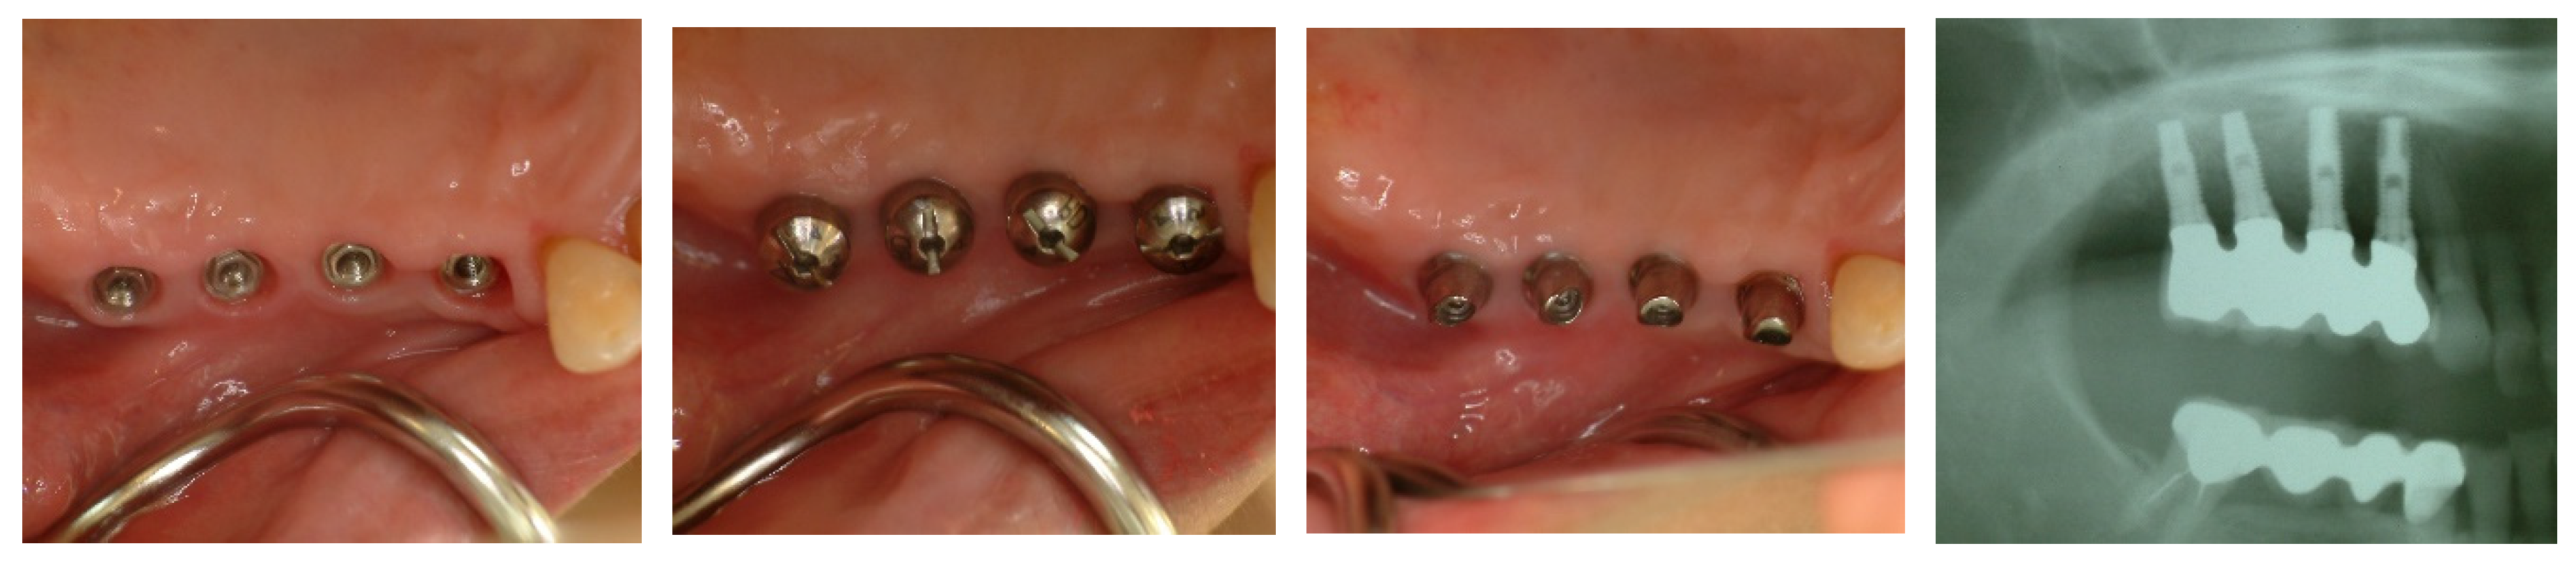

Figure 16. Transmucosal Soft Tissue Structures in Subcrestally Placed Implants. This figure presents clinical images showcasing the transmucosal area related to the junctional epithelium and connective tissue (the biologic width) in subcrestally placed implants (SPIs), captured either after the removal or before the placement of the prosthetic parts. Compared to epi- or equi-crestal implant placements, these SPIs exhibit a larger area of transmucosal soft tissue. The right image distinctly identifies three layers: the subcrestal zone, the Transitional Zone (TZ), and the marginal zone, where the pale pink color closely matches the adjacent oral epithelium.